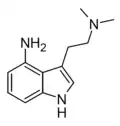

| 4-Amino-DMT [4] | artificial | 4-NH2 | CH3 | CH3 | 4-amino-N,N-dimethyltryptamine | 60331-61-5 |